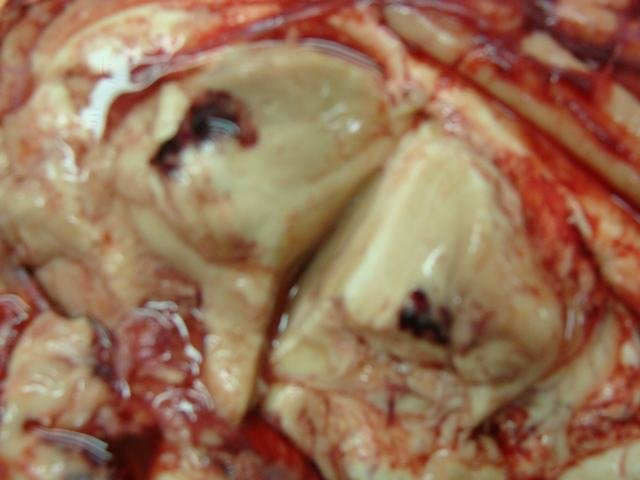

Traumatic Haemorrhage Thalamus 0

traumatic haemorrhage in thalamus